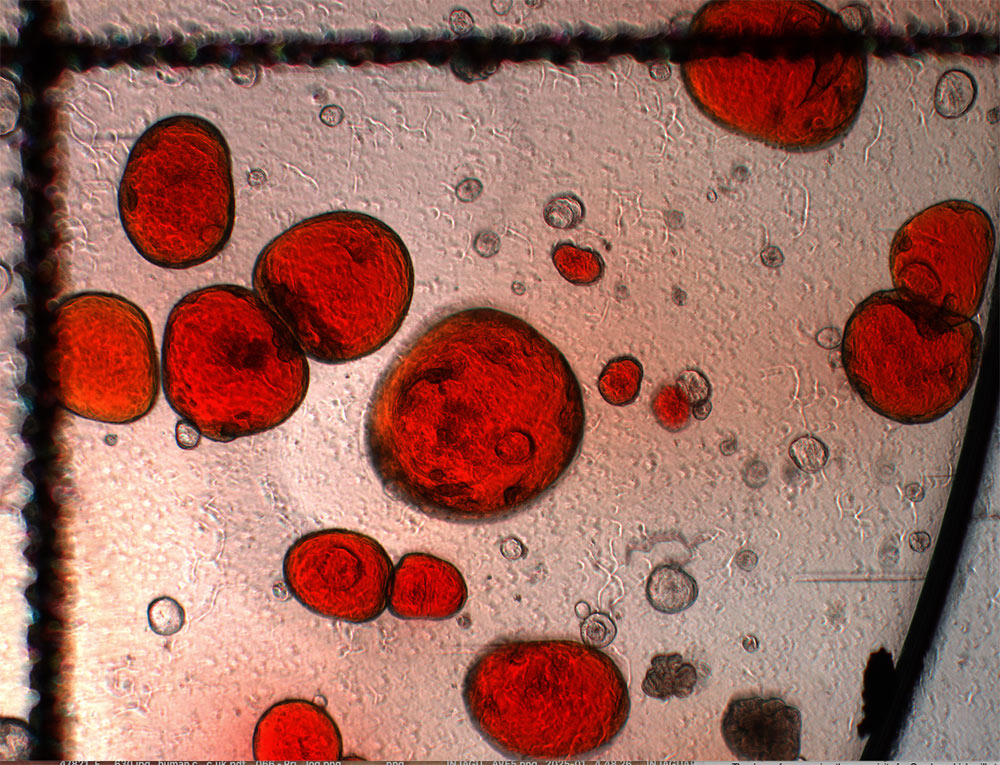

Placental organoids for TrophoSphere project – day 0 to day 16. Credit: Hongorzul Davaapil / Wellcome Sanger Institute.

The second project that we have been involved in is about placental organoids called TrophoSphere. The placenta is the first organ that forms during pregnancy, and it is foetal derived rather than maternal derived. It has a really big impact on how the pregnancy proceeds, whether there is a miscarriage, whether everything goes smoothly, or whether the woman develops complications such as preeclampsia. One of the main determinants is how deeply this organ embeds itself within the maternal endometrium. If it is too shallow, you might have problems where the foetus attempts to divert too many resources from the mother, and this can be difficult to manage in the case of pre-eclampsia. If it is too deep, it can also be problematic, for example, in the case of placenta accreta where there is risk of major haemorrhage following delivery.

For this project, led by Postdoctoral Fellow Dr Ana Paredes in Roser’s team, we have these immortalised trophoblast stem cells, which are specialised cells that can differentiate into various placental cell types. Using these we can create two types of organoids: ones that are non-invasive – they grow in their own little space, and don’t migrate – and ones that are highly invasive. They start off round, and then they eventually start creating these tendrils that would seek out the maternal endometrium to be able to attach and adhere. They are very different phenotypes, and they are very striking in how they look.